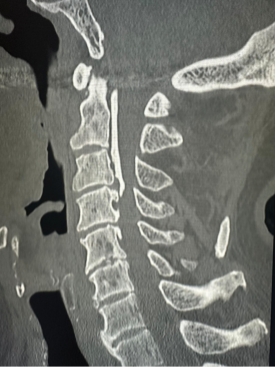

Common diagnostic tests include:

- X-rays (to assess spinal alignment and bending points)

- CT scans (for bony structures and abnormalities)

- MRI scans (to examine nerve and soft tissue damage)